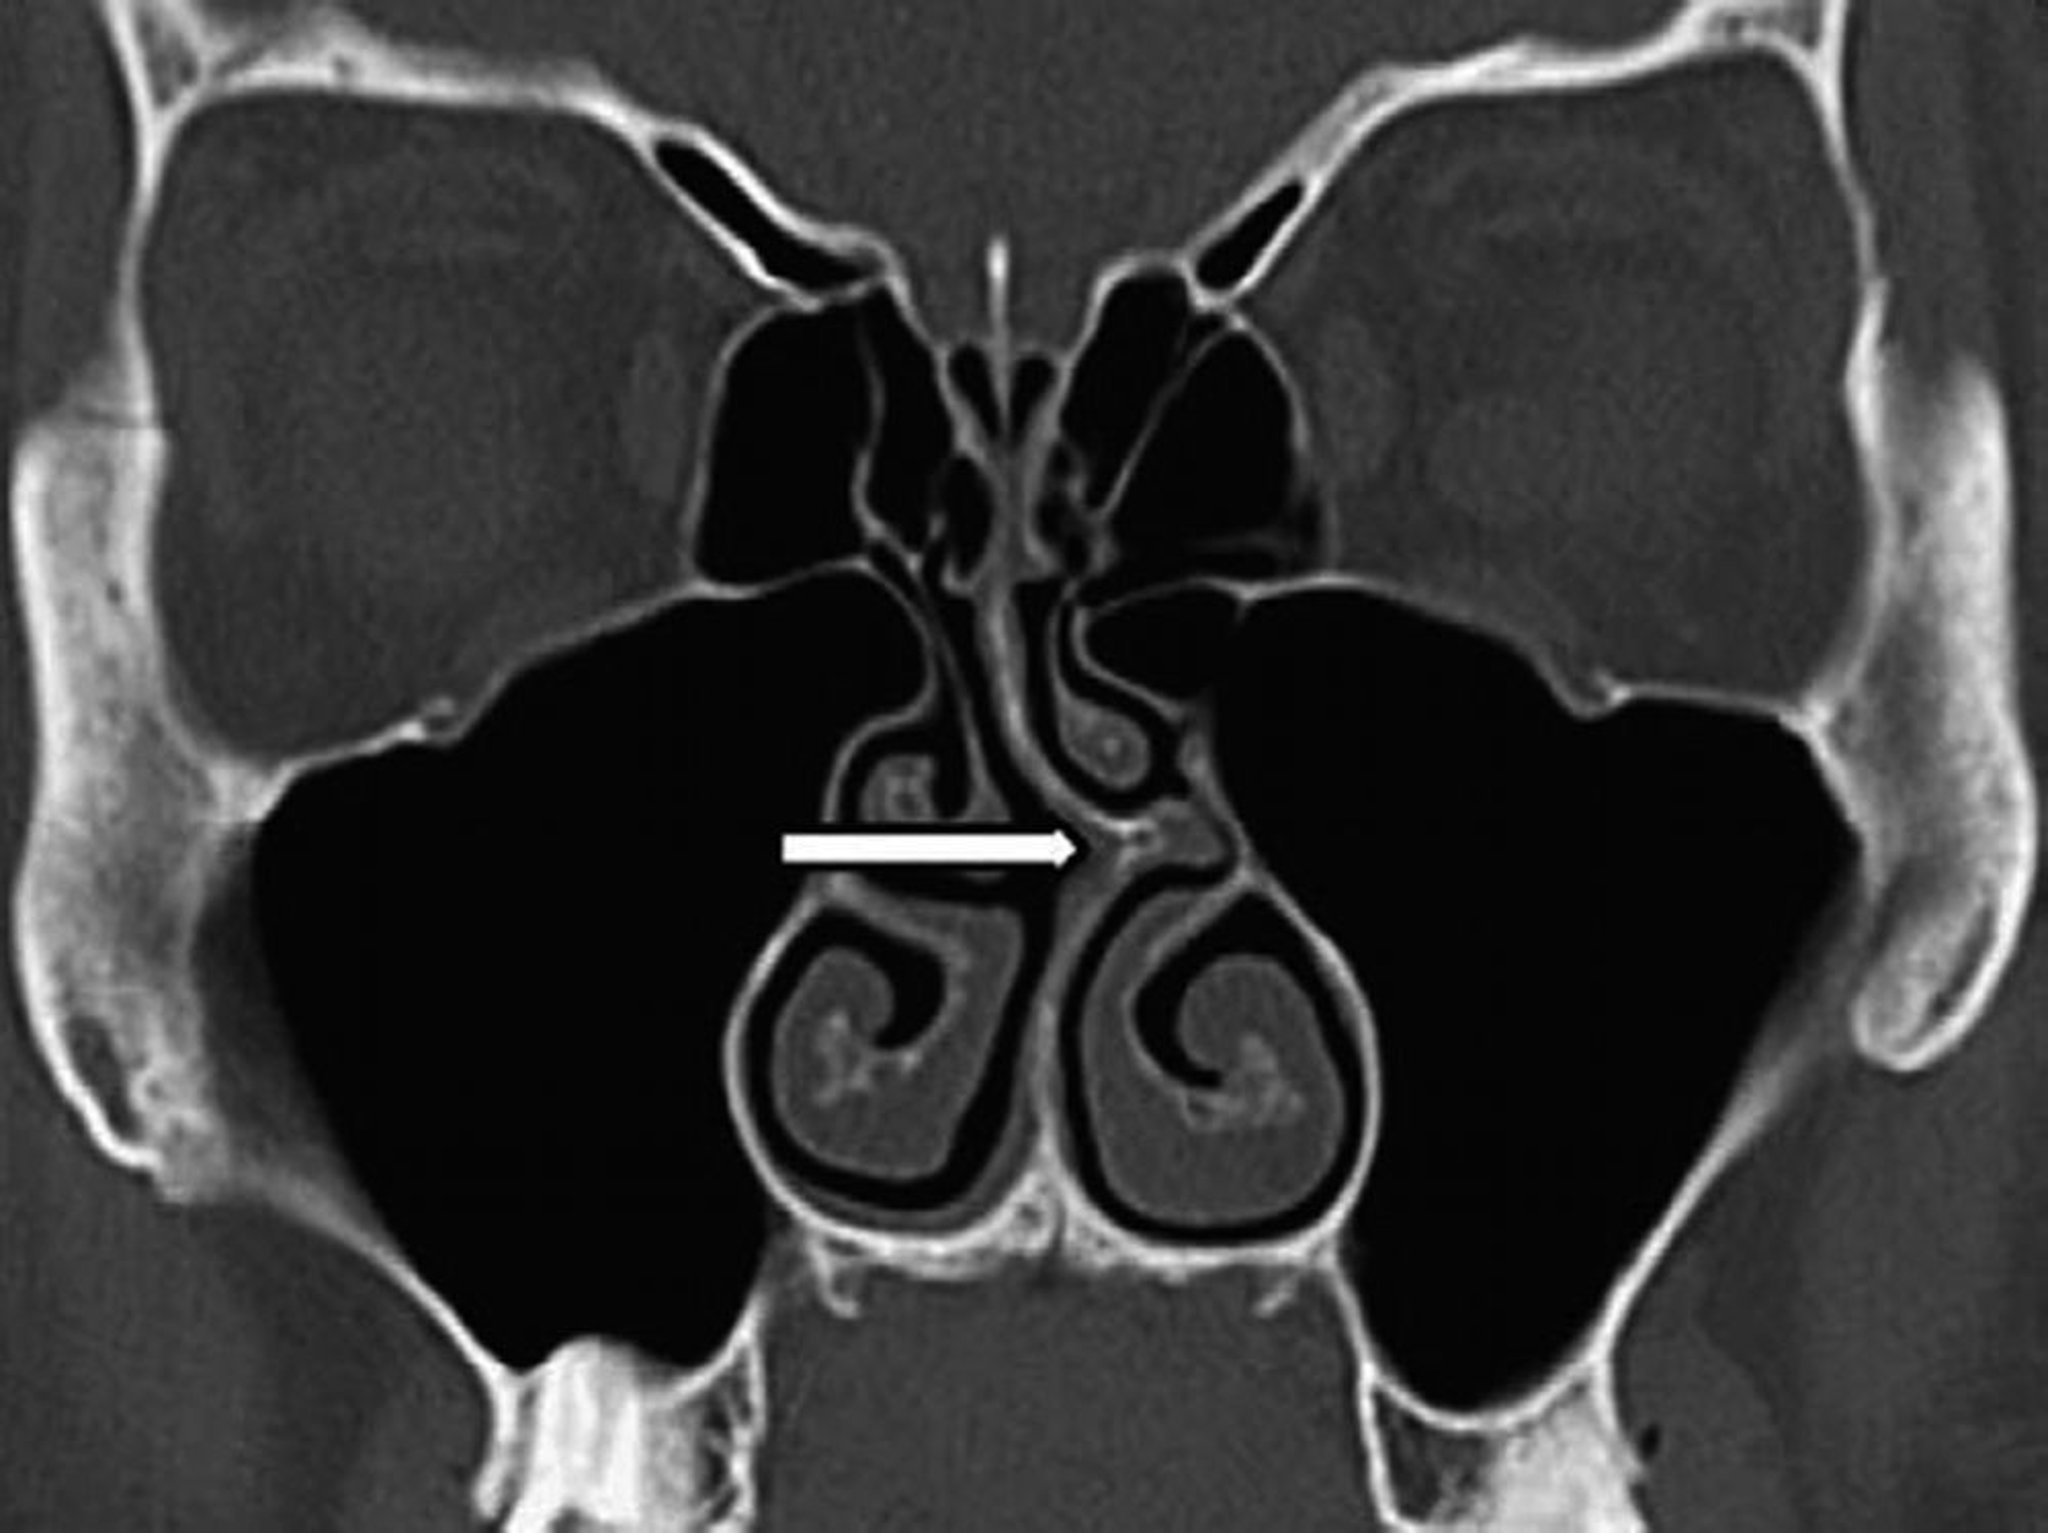

Искривление перегородки носа (КТ)

На этой КТ-сканограмме во фронтальной проекции показано искривление носовой перегородки влево (стрелкой).